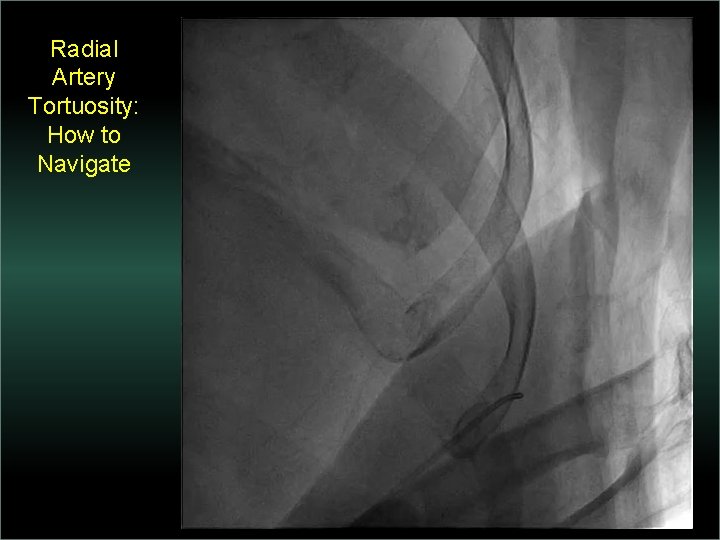

Transradial Interventions Difficult Anatomic Substrate Challenges and Solutions